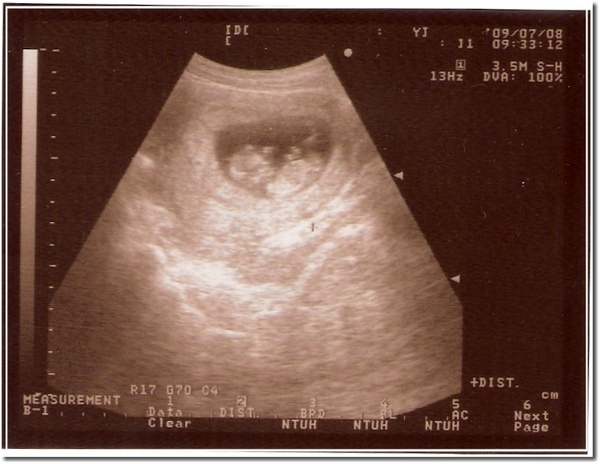

98/07/08 第三次超音波,第一次正式產檢,大約11週多

98070802.jpg

3ca8b998.gif 這次照超音波已經看得到雛型了唷~

還且還會像小蝦子一樣跳起來

第一次感覺到真的有一個小生命在肚子裡成型了

這感覺真的很奇妙